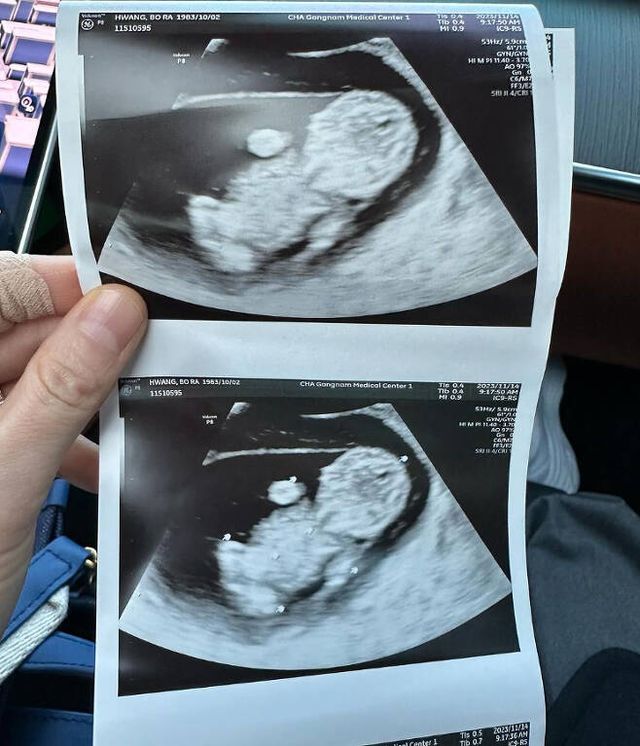

난임 고백 후 많은 이들의 관심이 모아진 가운데, 황보라는 임신 소식을 발표해 축하를 자아냈다. 태명을 '오덕이'라고 밝힌 황보라는 소속사 유튜브 채널 웤톸을 통해 임신 과정을 기록, '오덕이 엄마' 콘텐츠로 많은 사랑받았다.

이후로도 임신 기간 동안 다양한 이벤트를 하나씩 남기며 뱃속 오덕이의 성장을 공유한 황보라. 출산 직전까지도 떨리는 마음을 나누며 엄마가 될 준비를 이어갔다.